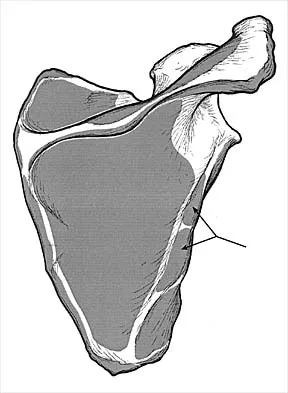

Which of the following nerves innervates the muscle that originates from the middle third of the dorsal surface of the lateral border of the scapula, as shown in Figure 7?

Explanation

Teres minor originates from the middle third of the dorsal surface of the lateral border of the scapula. It is supplied by the axillary nerve (C5). Williams PL, Warwick R, Dyson M, Bannister LH: Myology, in Gray's Anatomy, ed 37. Edinburgh, Scotland, Churchill Livingstone, 1989, pp 611-615.